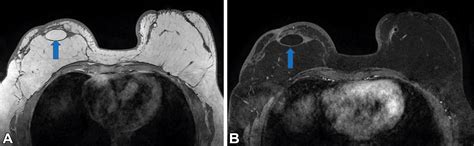

• Absence of Nipple Involvement: Imaging studies, such as MRI, must confirm that there is no evidence of cancer involvement in the ducts immediately behind the nipple.